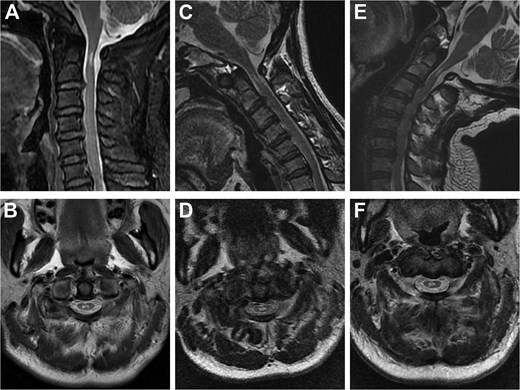

Cervical radiographs revealed hypoplasia of C1 but no evidence of atlantoaxial dislocation (Fig. 1). CT scans indicated bilateral bone abnormalities on the lateral sides of the posterior arch, particularly on the left side, with a midline cleft of the anterior arch (Fig. 2A). Three-dimensional reconstruction further demonstrated this abnormality (Fig. 2B–D). T2-weighted MRI revealed an intramedullary high signal at the C1 level, but no compression of the cord was observed (Fig. 3A and B). Cervical flexion-extension imaging indicated minor stenosis of the upper cervical spinal cord in the neck flexion position, but this alteration was not substantial (Fig. 3C–F). We considered that the high signal may be related to the repeated subtle activity of the posterior atlantoaxial arch in the past over a long period of time.

Sagittal and axial T2-weighted MRI of the cervical spine. (A, B) Supine neutral position. (C, D) Supine neck flexion position. (E, F) Supine neck extension position.